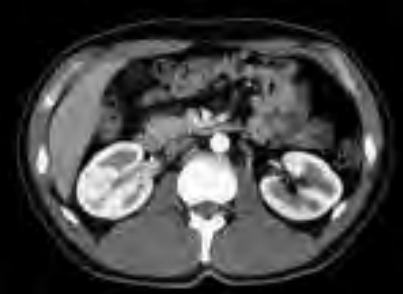

Które badanie zostało zarejestrowane na przedstawionym radiogramie?

Ilustracja do pytania 31

A. Dróg żółciowych metodą cholangiografii śródoperacyjnej.

B. Płuc wykonane metodą Przybylskiego.

C. Jamy brzusznej wykonane poziomą wiązką promieniowania.

D. Układu moczowego z użyciem środka kontrastującego.